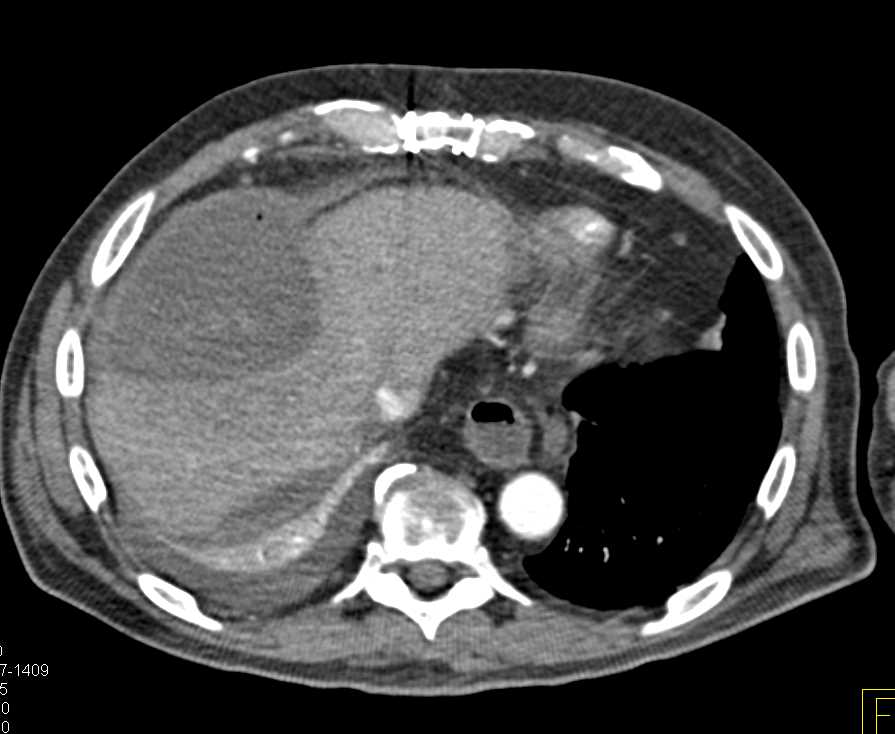

Biloma with Active Bleed